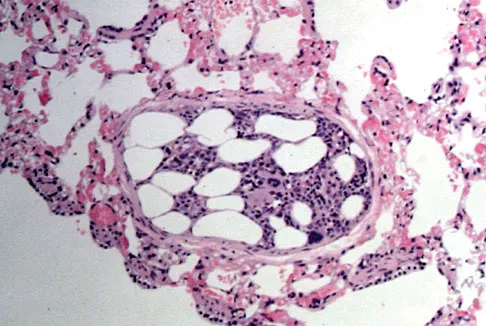

Figure 49 shows a histologic section of the lung in a patient who died during total hip arthroplasty. What unexpected finding is seen in the pulmonary capillaries?

Explanation